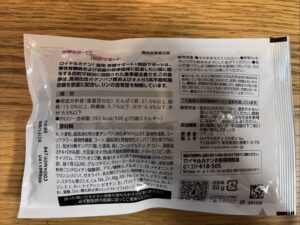

◾️処置処方

安定化サプリメント ジルケーン10日

腎臓➕脳の興奮を抑える作用フードサンプル